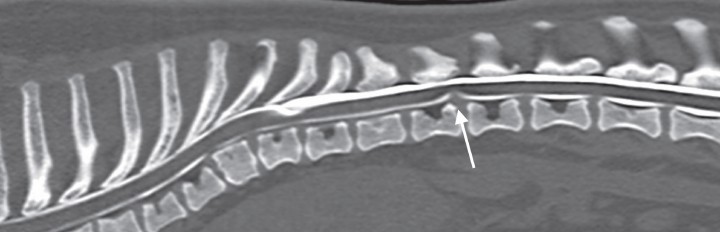

Las cavitaciones se observaron en los segmentos medulares adyacentes (1 ó 2 vértebras craneal o caudalmente) a malformaciones óseas congénitas, tales como hemivértebras, vértebras en mariposa, o displasias articulares, en 7 de los 13 casos analizados. En 4 de los 13 casos encontramos ligeras protrusiones discales cercanas al segmento afectado sin significado clínico aparente, ya que el área de la sección transversa de la médula era menor en el lugar de la cavitación que donde se encontraban las protrusiones (Fig. 3).

<p>Reconstrucción sagital de mielo-TAC del caso 5 con algoritmo hueso donde se observa una protrusión discal en T12-T13 (flecha) cercana al lugar de la cavitación leptomeníngea.</p>

Figura 3

Reconstrucción sagital de mielo-TAC del caso 5 con algoritmo hueso donde se observa una protrusión discal en T12-T13 (flecha) cercana al lugar de la cavitación leptomeníngea.